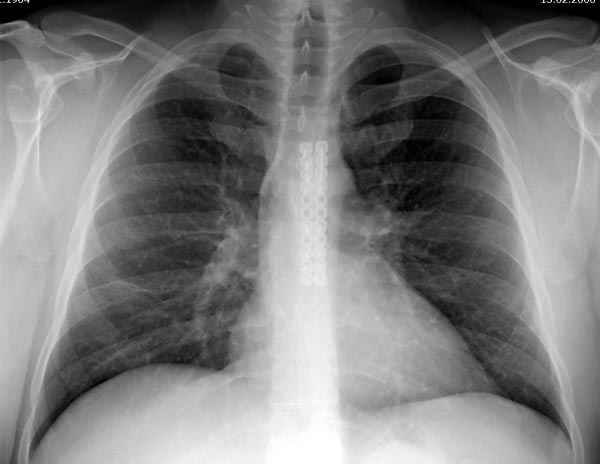

Может, имелись ввиду нарушения, связанные с изменением конфигурации средостения после эстетических операции на грудной клетки при врожденных: килевидных и воронкообразных деформациях, но в данном случае, кроме болевого синдрома, не думаю, что несросшиеся перелом грудины окажет серьёзное влияние на кардио-респираторные функции.

Пару лет назад коллега из грудной хирургии направил больного с хроническими жалобами на боли по поводу ложного сустава грудины.

Оперировали вместе с грудным хирургом и в нашем случае главной причиной была болезненность. Во время операции приняли все меры предосторожности недопущения прокола средостения (см. на 4 снимке близкий контур сердца!!)

Ложный сустав зафиксирован двумя пластинами 2.4 мм (locking plate) позаимствованными из челюстно-лицевой хирургии, с костной пластикой, все остальные пластины мне показались слишком толстыми, грубые для грудины или отсутсвовали возможности создания угловой стабильности.

Рентген снимки во время операции и последние сделаны на днях.